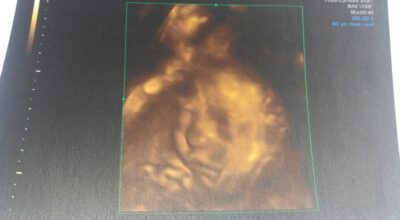

Isabella